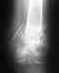

год назад, может быть больше, неправильно сделал элемент и упал на плечо и было много хрустов слышно... я не пошел тогда в травмпункт, хотя у меня ключица преподнялась и руку не мог поднимать. но со временем через месяц-2 прошло все это и осталась только шишка около ключицы у плеча.

недавно я на тренировке прыгнул винт и перекрутил его и упал на то же самое место как и год назад (на плечо) был 1 большой мощный хруст. решил пойти в травмпункт и мне сказали там что у меня внутренний перелом ключицы и разрыв связок...( теперь не знаю что делать... гипс если возможно или операция, но у меня щас этот месяц сессия(((